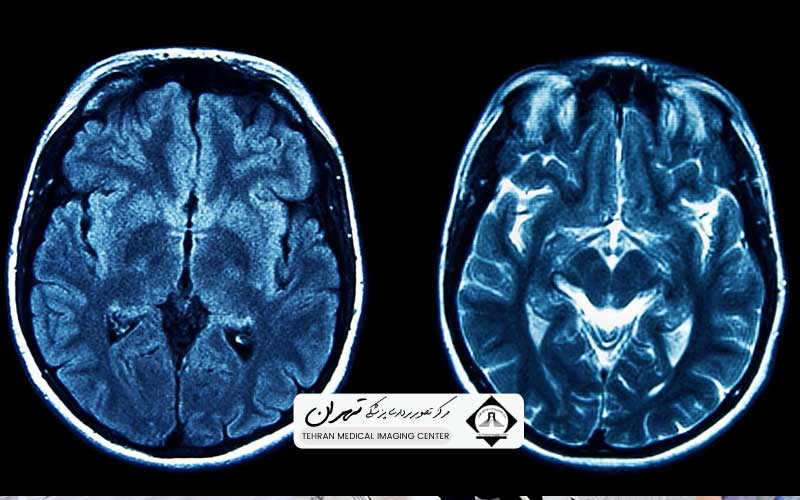

تصویربرداری تشدید مغناطیسی (MRI) سر، یک ابزار تشخیصی فوقالعاده قدرتمند و غیرتهاجمی است که با استفاده از میدانهای مغناطیسی قوی و امواج رادیویی، تصاویر دقیقی از ساختارهای نرم مغز، ساقه مغز و مخچه ارائه میدهد. این تصاویر سه بُعدی، اطلاعات حیاتی درباره وضعیت سلامت عروق، بافت عصبی، شناسایی تومورها، سکتههای مغزی، بیماریهای دژنراتیو مانند اماس (MS) و ناهنجاریهای ساختاری را در اختیار پزشکان قرار میدهد. با توجه به اهمیت حیاتی این اطلاعات در مسیر تشخیص و طرحریزی درمان، سهم این روش در حفظ سلامتی و کیفیت زندگی بیماران غیرقابل انکار است.